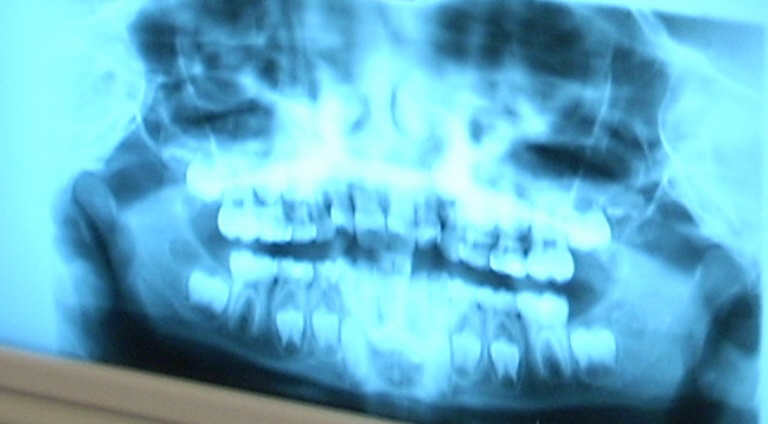

Besonders interessant war ein Röntgenbild mit Milchzähnen und bleibenden

Zähnen im Kiefer. Wir wissen jetzt, dass Milchzähne doch Wurzeln haben!